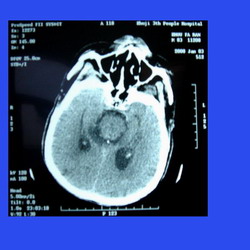

缺氧CT圖1、原因

急性缺氧可引起頭痛、情緒激動,思維力、記憶力、判斷力下降或喪失以及運動不協調等。嚴重缺氧可使腦組織發生細胞腫脹、變性、壞死及腦間質水腫等形態學變化,這與缺氧及酸中毒使腦微血管通透性增高引起腦間質水腫有關。這些損傷常常在缺氧幾分鐘內發生。且不可逆。腦血管擴張、腦細胞及腦間質水腫可使顱內壓增高,由此引起頭痛、嘔吐、煩躁不安、驚厥、昏迷,甚至死亡。慢性缺氧則易疲勞、嗜睡、注意力不集中等症狀。

所謂高原腦水腫(highaltitudecerebraledema,HACE)發病機制除了缺氧引起腦血管擴張、腦血流增多外,可能還與下列因素有關。1)腦細胞水腫;2)血腦屏障功能受損,3)腦靜脈內血栓形成,進一步加重腦水腫形成。